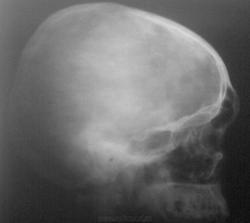

Виктор Григорьевич, надеюсь простите некоторые вольности (попыталась немного улучшить Ваши рентгенограммы), но всё равно, кроме пристеночного затемнения гайморовых пазух пока ничего не нахожу.

раз никто не комментирует - значит сложная задача, дайте хоть какую подсказку, что за инородное тело?

Подсказка 2-я - это резиновая пуля

Случай потому и представлен, что порой такую "резинку" практически не найти....